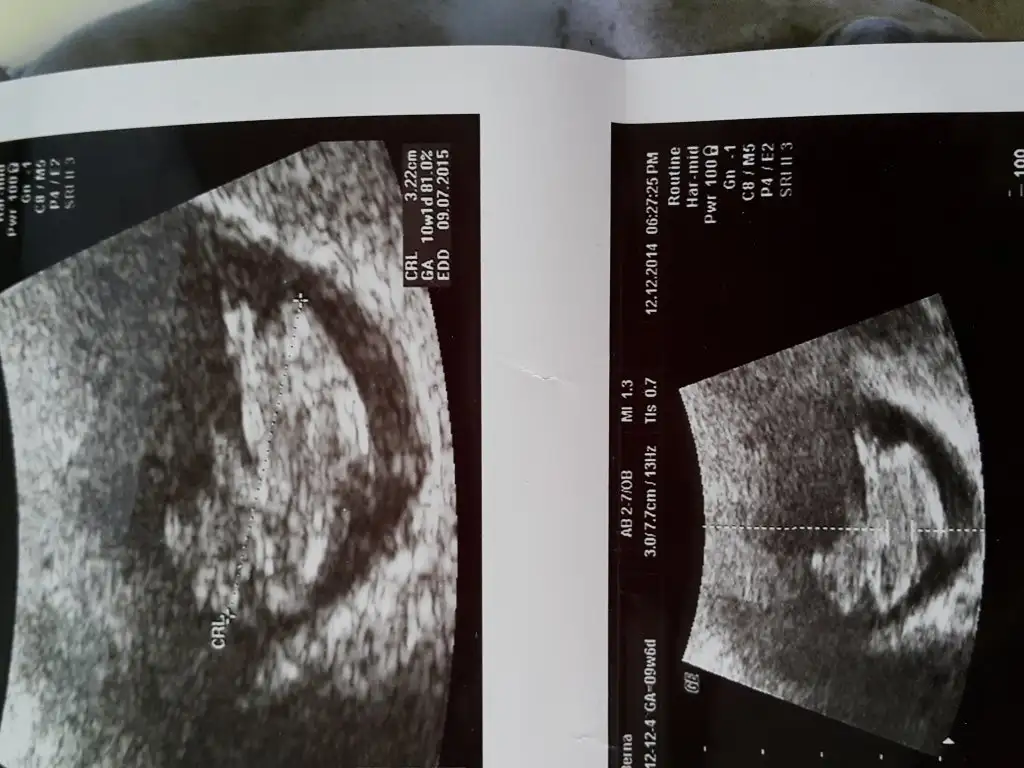

cnm bu fotodo 10 haftalık felan anladığım kadarıyla bu haftada ikisi de aynı nuba sahip göremeyik yani 13 olsun ekle olur muEki Görüntüle 1334521 Eki Görüntüle 1334521

Gunaydin arkadaslar.dun kontrolum vardi.9+4 olmaliydim .10+1 misim.cok merak ediyorum melegimin cinsiyetini.yorumlarsaniz duaciniz olurum

Sagol canim yorumladigin icin.10 haftalik belli olan vardi.bi umut sordum ben de.mecbur bekljycem artikcnm bu fotodo 10 haftalık felan anladığım kadarıyla bu haftada ikisi de aynı nuba sahip göremeyik yani 13 olsun ekle olur mu